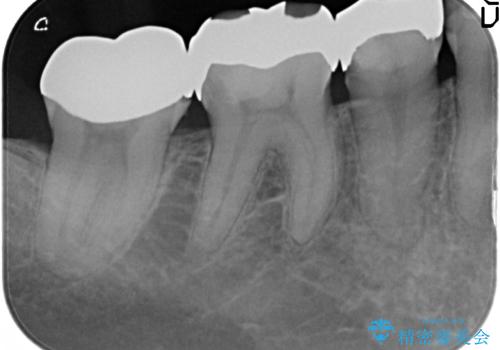

- 右下奥の銀歯3本をオールセラミッククラウンで治療した症例です。

右下6は失活(神経が死んでいる状態)していたため根管治療を行いました。

今回用いたオールセラミッククラウンは、ジルコニアフレームという白い素材の上にセラミックを盛っているため審美性が非常に高いのが特徴です。

またジルコニアは人工ダイヤモンドの材料にも使われているほど高い強度を持っており、そのためオールセラミッククラウンは審美性だけでなく、奥歯やブリッジの補綴も可能とするクラウンです。